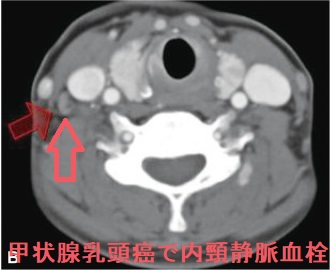

甲状腺癌分化癌(乳頭癌、濾胞癌)の脳転移は遠隔転移の約1%。脳神経症状・けいれんを起こし予後に大きく影響。単発性の場合は原発性脳腫瘍と鑑別できず、摘出後の病理標本で甲状腺乳頭癌・甲状腺癌濾胞癌の脳転移と分かる。最初から放射性ヨウ素(I-131)を取り込んでいれば放射線内・外照射、γナイフ、分子標的薬で治療。下垂体腫瘍で中枢性甲状腺機能低下症(非機能性下垂体腫瘍のほとんどが血清TSH基準値内)。ACTH産生腫瘍は中枢性甲状腺機能低下症を起こし易く、成長ホルモン(GH)産生腫瘍(先端巨大症)は起こし難い(いずれも約50%で血清TSH基準値内)。

甲状腺癌の脳転移は約1%と稀。半数が甲状腺未分化癌、もう半数が甲状腺癌分化癌(乳頭癌、濾胞癌)[J Neurooncol. 2001 Jan;51(1):33-40.]。

甲状腺癌脳転移の診断は、

- 脳CT/MRI